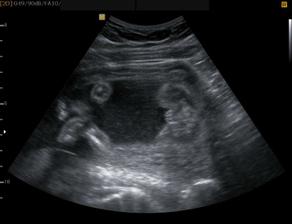

Jak rosteme s Aničkou v bříšku ;o)